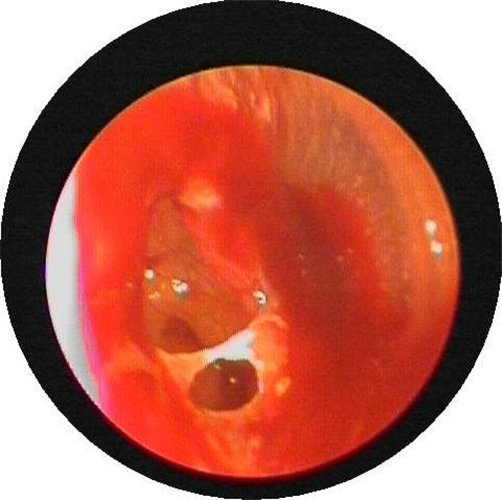

外傷性破裂鼓膜穿孔

外傷鼓膜穿孔

外傷使鼓膜穿孔

外傷性的鼓膜穿孔